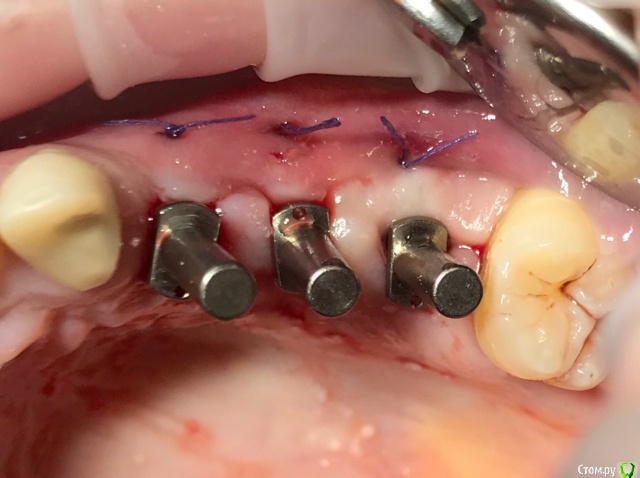

колесников Опубликовано 20 августа, 2019 Автор Поделиться Опубликовано 20 августа, 2019 Очередной случай тоннельной пластики альвеолярного гребня. Был небольшой бонус в виде лунки 26го зуба с дефектом вестибулярной стенки и оас. Лунка консервирована и закрыта «быстрым Ноймайером»,24,25 тоннельный графтинг. Графт тот же,шурос кортикальный без добавок.Контроль и имплантация через 4 мес,через неделю фиксация временной реставрации. Через 2-3 проверим на состоятельность. 4 Ссылка на комментарий

колесников Опубликовано 27 сентября, 2019 Автор Поделиться Опубликовано 27 сентября, 2019 Улучшение объема и качества мягких тканей в пришеечной области у ранее поставленных имплантов ,посредством тоннельной костной пластики. Объём 0,5г. Вид через 6 мес. 3 Ссылка на комментарий